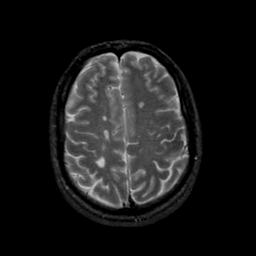

MR Study #23, January 26, 1992 -- Slice #37